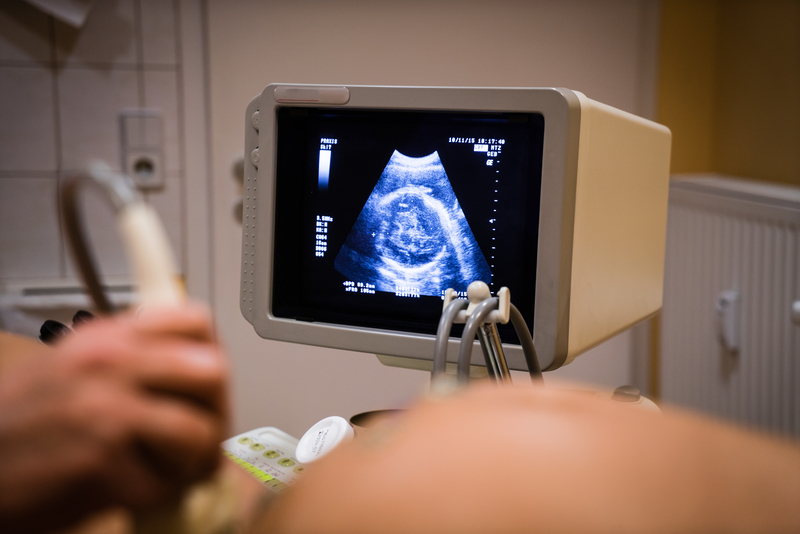

Parents have many decisions to make when making preparations for a baby’s arrival, whether or not to add cord blood to this list is important to consider. Umbilical cord blood cells are genetically unique and are the building blocks of the baby‘s immune system, tissue, organs, and blood.

Families with a history of genetic diseases are advised to bank the cord blood of their baby. The move is recommended in a bid to ensure such a family will be able to get high-quality treatment should any genetic disease affect their baby or a member of the family. Cord blood banks in the country offer many families options they can use to save this blood. Since there is a short window of opportunity to collect these cells, the tissue and blood should be collected within a few minutes after childbirth. Parents need to make the decision whether or not to save these cells within the third trimester. Early preparation will ensure the collection kit and other requirements are handled before the baby’s arrival.